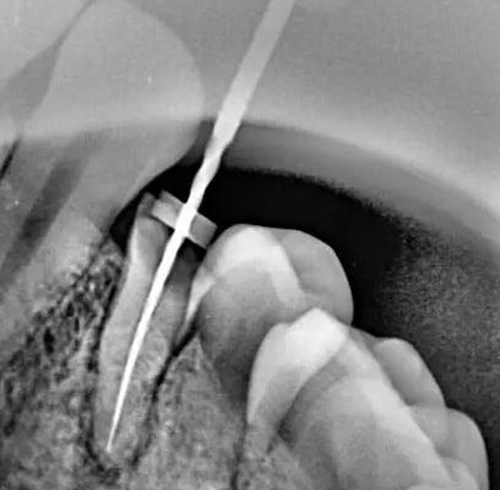

牙根內外吸收的原因不同,治療方法和預后也不一樣。因此,應根據X線和臨床表現(xiàn),區(qū)別內外吸收,選擇適應的治療方法,用X線根尖片和咬合片的表現(xiàn)區(qū)分牙根內外吸收;內吸收邊界清楚光滑,形狀多對稱,吸收部位根管粗大;外吸收邊界粗糙,密度不一,呈蠶食壯,形狀多不對稱,在破壞未穿通根管前,仍能尋找到根管的原始輪廓。偏移投照時,內吸收與根管的位置關系不變,而外吸收部位發(fā)生變化。

內吸收是從髓腔或根管內壁開始,與牙髓炎癥和細菌感染有關。一般無癥狀,多為X線照相時發(fā)現(xiàn)。應盡早行根管治療,去除感染組織后,預后良好,否則進一步發(fā)展會造成根管壁的穿孔。徹底去除內吸收部位的感染組織較為困難,充分沖洗或超聲蕩洗是有效的清潔方法,并在根管內封Ca(OH)2蝴劑1周后再根充。由于內吸收過大,根管壁很薄,應避免過大壓力,要選用Ca(OH)2基質的蝴劑與牙膠根充,根管壁穿孔較小,可用 Ca(OH)2糊劑根充3個月,誘導硬組織形成后再根充;或用根管水泥(MTA)根管內根充并修補。較大的根管壁穿孔可用MTA從根管內或手術修補。內吸收近根尖區(qū)可考慮根尖手術,多根牙可考慮截根術。

牙根外吸收是從牙周組織開始,原因多為創(chuàng)傷,矯正力過大,埋伏牙,牙齒漂白,再植牙和根尖周炎癥等。因根尖周炎造成的根尖區(qū)外吸收處理方法同內吸收,其他因素造成的外吸收采用相應的對因處理和根管治療。